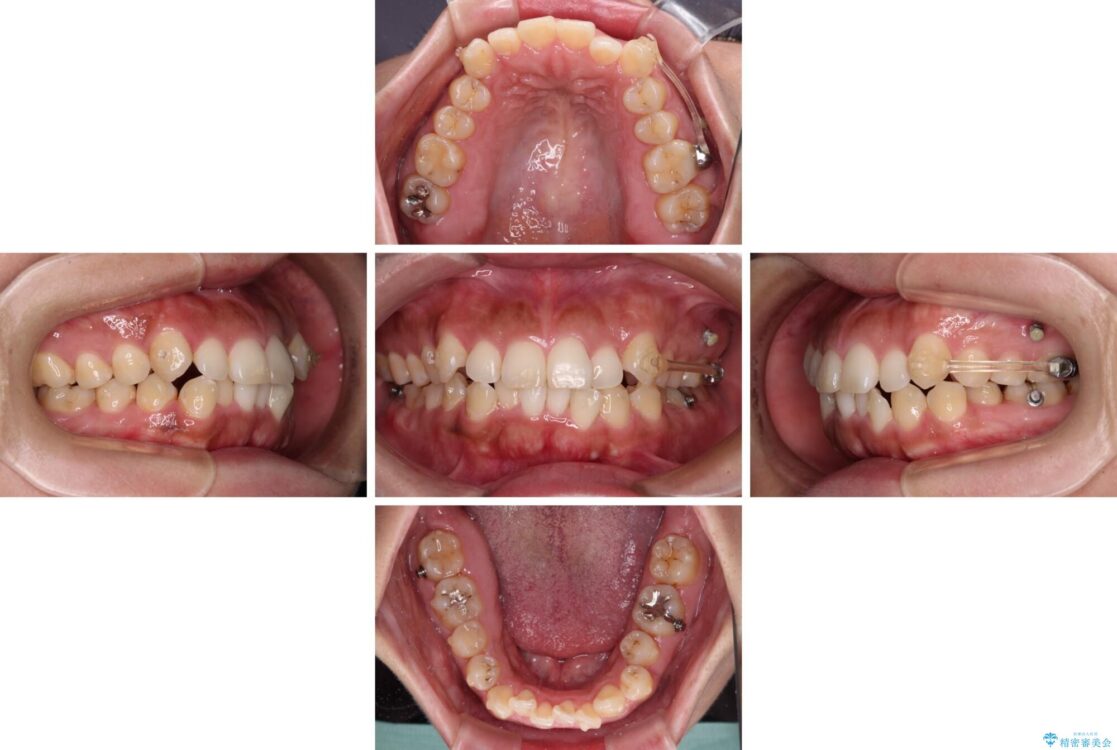

治療途中

• 【モニター】カリエール・ディスタライザーを併用した八重歯のインビザライン矯正 治療途中画像

インビザライン単体で改善することも可能ですが、八重歯とその後方にある歯列を確実移動させないと、上下正中がずれてしまう可能性があります。

インビザライン単体での治療ではなく、カリエール・ディスタライザーという補助装置を併用して、より確実性を上げることとしました。

補助装置で八重歯を解消しながら、並行してインビザラインで歯列を整えることとしました。